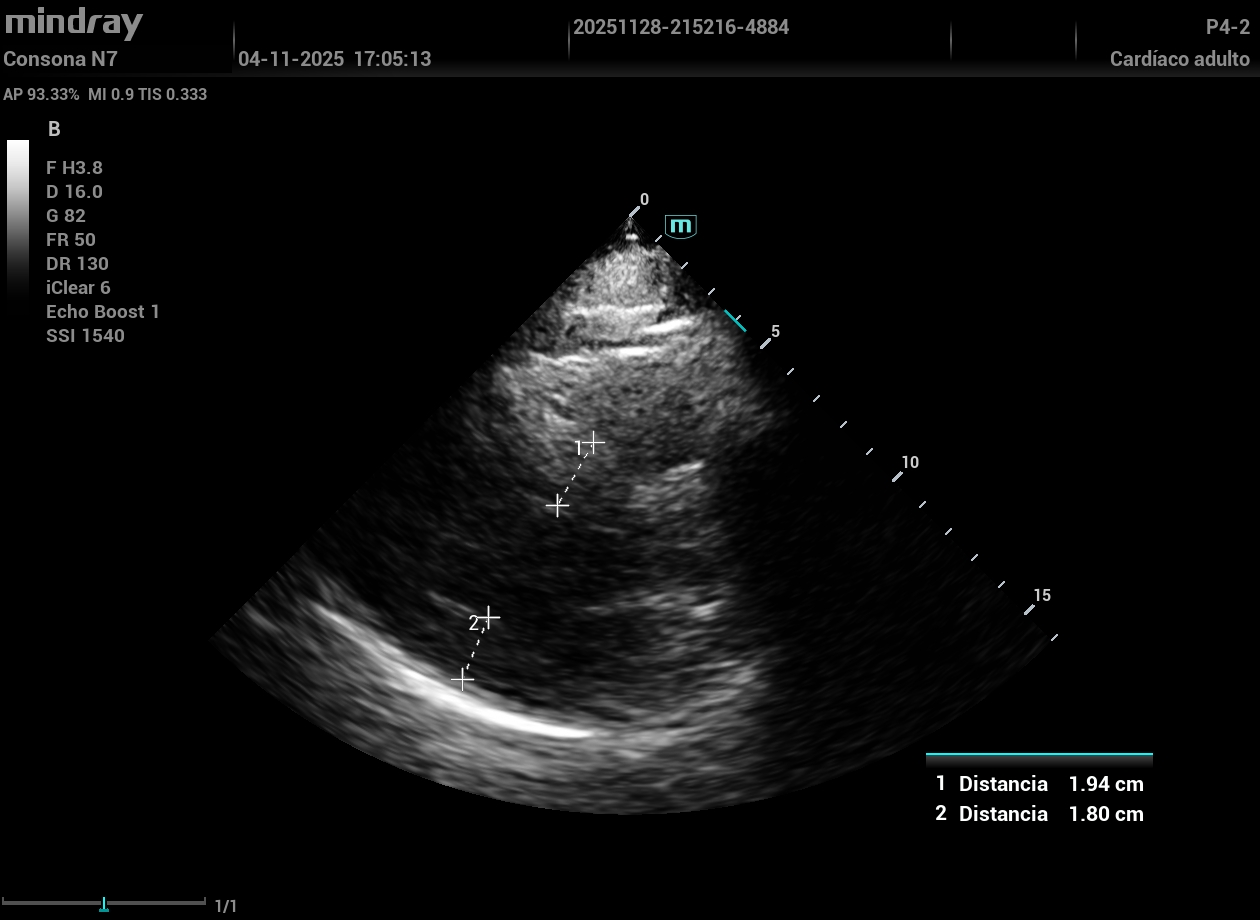

Eco vascular protocolo VASUS +: grandes placas de ateroma tipo 2-3 en ambas carótidas visualizando en carótida interna derecha una obstrucción de más del 50%; ambas femorales con alta carga de placas. ETT: FEVI conservada. HVI concéntrica.